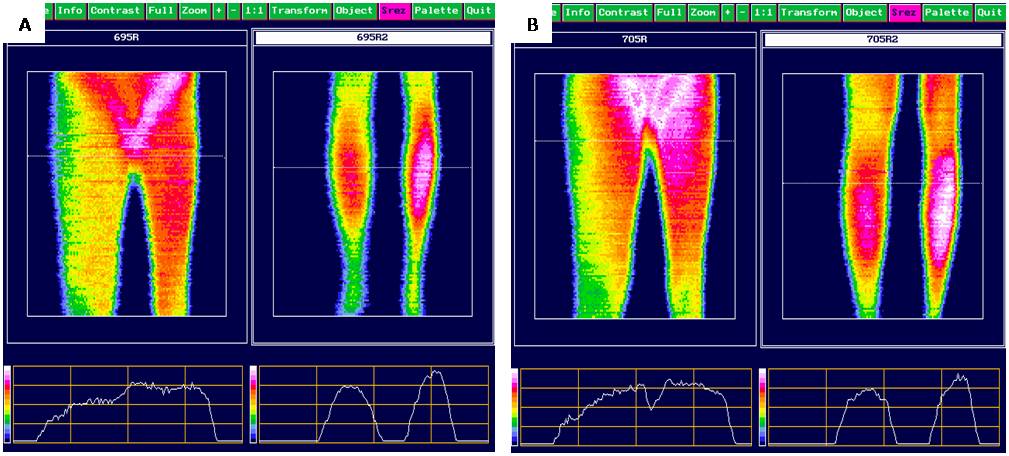

With a high level of objectification, the following changes of the quantitative parameters of infrared radiation of a pathologically altered limb were obtained: left inguinal region — 39.02 ± 0.17°С, popliteal region 37.86 ± 0.13°С, respective regions on the right — 37.93 ± 0.16°С and 38.96 ± 0.19°С. The thermal asymmetry was characterized by peculiarities of arrangement of vessel trunks and innervation of the limb (Table 4). Evaluation of thermography parameters of LL showed increase in the level of IR radiation only in Group 2. Increase (р < 0.001) in the area of hyperthermia in the distal part of lower legs and along the inner surface of thighs was recorded evidencing improvement of microcirculation (Figure 1).

Fig. 1. Clinical example: Thermograms of lower limbs of a female patient S., 58 years old, with III stage secondary lymphedema before (A) and after (B) comprehensive treatment.